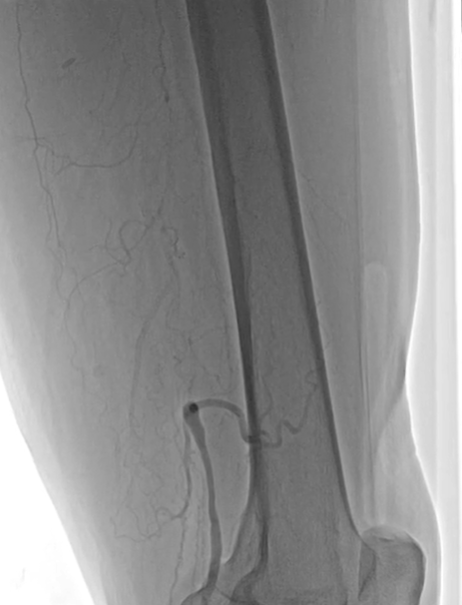

手术当天,在局部麻醉下行下肢动脉造影,提示股浅动脉近端形成无残端闭塞,闭塞长度达惊人的 40 cm,这就意味着全程都需要「摸着石头过长江」。由于闭塞长度过长且复杂,杨征副主任医师果断启动 DSA 及超声导引双指引确保手术安全性。

在功能科王艳夏医师的辅助下,手术团队与导管室李锐主管护师、鱼祥护师通力合作,同时建立正向、逆向通路,使用多种心脏泛血管技术最终应用 TIP-IN 成功双向「会师」,面对「坚如磐石」的病变,将仅有头发丝粗细的导丝顺利通过靶病变到达远端动脉血管。沿导丝送入旋切系统,导管前端的高速旋转刀片如同「微型隧道盾构机」,精准地将血管内的斑块粉碎并同步抽吸出体外。后顺利置入下肢动脉药物球囊两枚进行双保险,大大降低血管出现再狭窄概率。整个过程耗时 6 小时,40 cm 的超长闭塞的血管成功恢复了通畅血流。(术者:杨征。助手:李臻、何涛志)